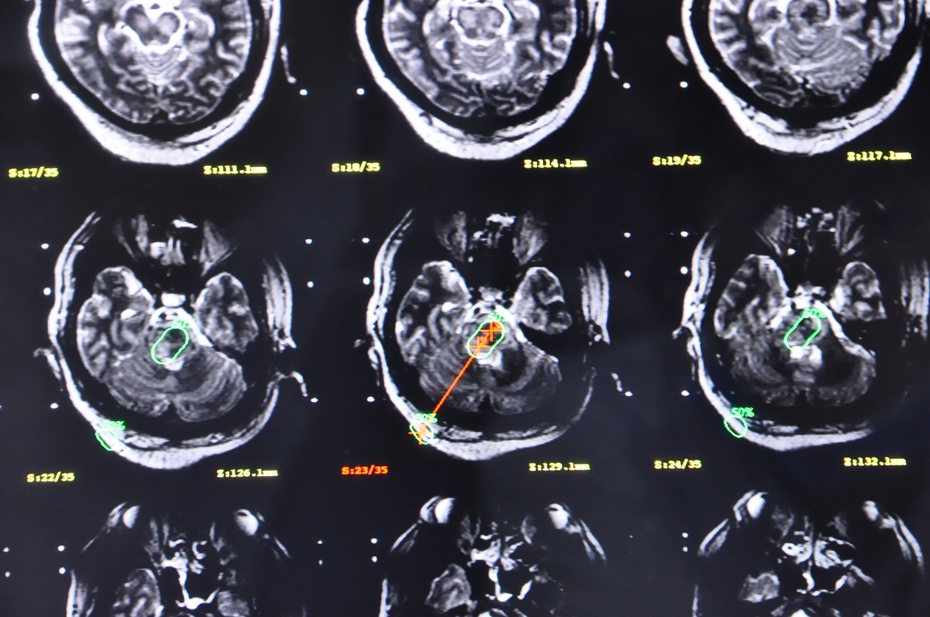

患者29岁急诊来院时已陷入深昏迷,血压达220/100mmHg,急查头颅CT见脑干内不仅已形成血肿,且出血仍有向桥脑下方和延髓方向继续侵袭倾向,患者随时有呼吸心跳停止的可能,病情十分危急。因送诊路上呕吐已经有误吸,紧急抢救,吸引出呕吐物才防止窒息死亡,并紧急降压、止血,稳定住了生命体征,为手术救治赢得了宝贵时间。在CT影像上到脑干中央有白亮的出血团影。右枕下仅切开2cm头皮小切口,钻开颅骨,从仅1cm直径的骨孔内用尖刀切开硬膜,电灼蛛网膜、避开横窦和皮层血管、确认小脑表面穿刺点……再次核对各项靶点数据后,闪亮的金属穿刺针从导向弓轻轻滑过,指向A点。

穿刺针轻推刺入,凭着手中细微感觉,进入小脑、穿过小脑、进入环池、进入脑干、到达血肿!整个手术室都屏住了呼吸…“麻醉注意心电监护!”进针精准地停止在零刻度靶心,拔出针芯、置管、抽吸,一股暗黑色的积血瞬间引出…